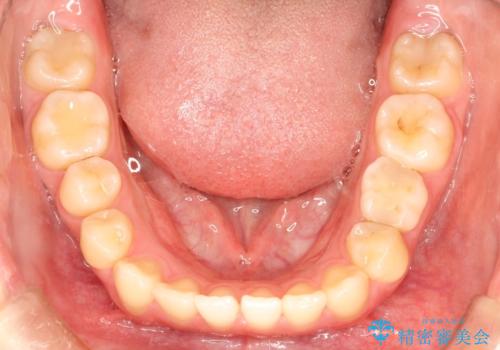

- 前歯の捻れを主訴に来院されました。

インビザラインを希望されておりましたが、20時間もつけることができなかったためワイヤー矯正にて叢生の改善を行っています。

右上の側切歯(前から2番目の歯)が90度程度ねじれている状態でしたが、1月に1回のワイヤー交換できれいに並ぶことができ満足いただけました。